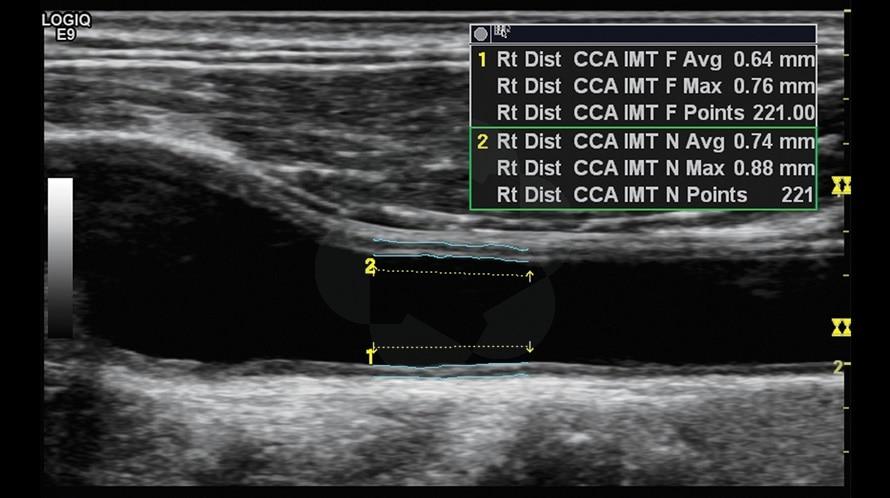

- Auto-IMT - автоматический расчет интима-медиа

Автоматическое измерение IMT